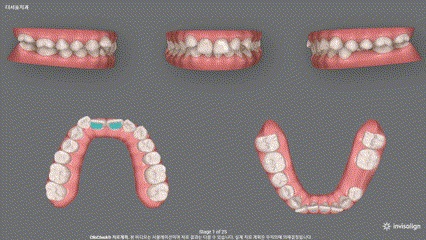

저는 위례 인비절라인 을 시작하기 전에

반드시 모든 환자에게 ‘클린체크’라고 하는

3D 시뮬레이션 영상을 보여드리는데요,

앞으로 이동할 예쁜 치열을 미리 보여드리니